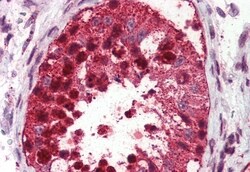

Invitrogen™ USP2 Polyclonal Antibody

Percent identity with other species by BLAST analysis: Human, Gorilla, Gibbon, Monkey, Marmoset, Mouse, Rat, Dog, Bovine, Hamster, Elephant, Panda, Horse, Rabbit, Opossum (100%); Pig (94%). Immunohistochemistry with formalin-fixed paraffin-embedded tissues requires pretreatment with Proteinase K.

| Applications | Immunohistochemistry (Paraffin) |